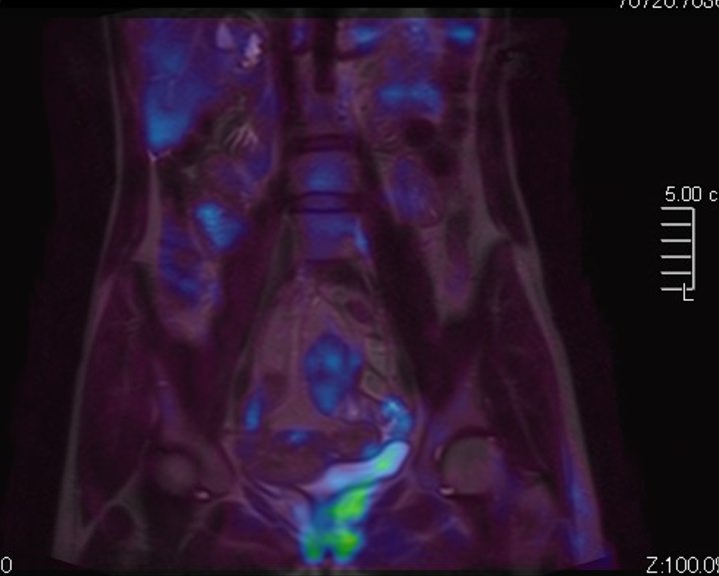

В сложных диагностических случаях, когда диагноз неясен, особенно при подозрении на множественные метастатические поражения, если при помощи других методов не удается выявить первичный опухолевый очаг, тогда врач может порекомендовать МР-скрининг всего тела.

Метод позволяет выявить бессимптомные потенциально опасные для жизни состояния, например опухолевые образования, которые долгое время себя никак не проявляют и могут обнаруживаться уже в запущенных случаях. К примеру, опухоли яичников, почек, печени, когда раннее выявление процесса значительно повышает шансы пациента на успешное лечение и выздоровление. Также МР-скрининг может проводится в профилактических целях пациентам, у которых есть близкие родственники с онкопатологией, чтобы вовремя выявить начало болезни.

• При проведении онкопоиска, когда необходимо найти первичный очаг опухоли.

• При подозрении на множественные метастазы с поражением головного мозга и внутренних органов.

МР-скрининг проводится без контрастного усиления. Если во время процедуры врач-рентгенолог выявит зоны патологически измененного МР-сигнала, то вторым этапом станет повторное проведение диагностики, но уже прицельно той области, где были выявлены изменения. Повторное исследование оплачивается отдельно и проводится в другой день, как правило, с применением контрастирования.

МРТ с контрастом необходима для получения более точных сведений о структуре, размере, распространенности патологического процесса и некоторых других его параметрах (например, является ли он опухолевым)